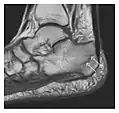

High-energy trauma fractures

Figure 1: A 56-year-old woman presenting with left knee pain after a fall. (a) Initial anteroposterior radiograph was considered normal, however, subtle cortical disruption of the anterior rim of the medial tibial plateau, medial to the tibial spine, is noted (arrow). (b) Coronal T1-weighted MRI confirms the cortical disruption (arrow) and shows extensive fracture through the proximal tibia. (c) Coronal proton density-weighted image with fat saturation shows extensive edema in the subchondral bone. Note also hypersignal adjacent to the medial collateral ligament corresponding to a grade I sprain (arrowheads).[1]